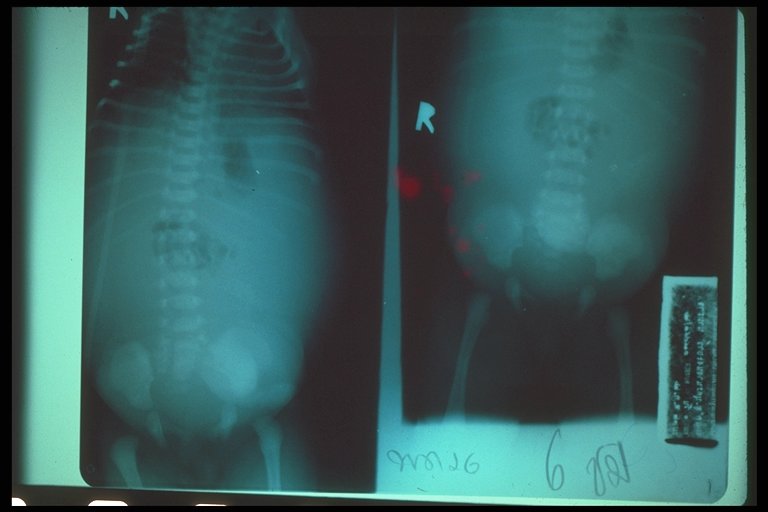

Meconium peritonitis. A classical abdominal X-ray demonstrates calcified extravasated meconium in the peritoneal cavity since fetal growth. Free air in the abdomen (football sign) is also noted.